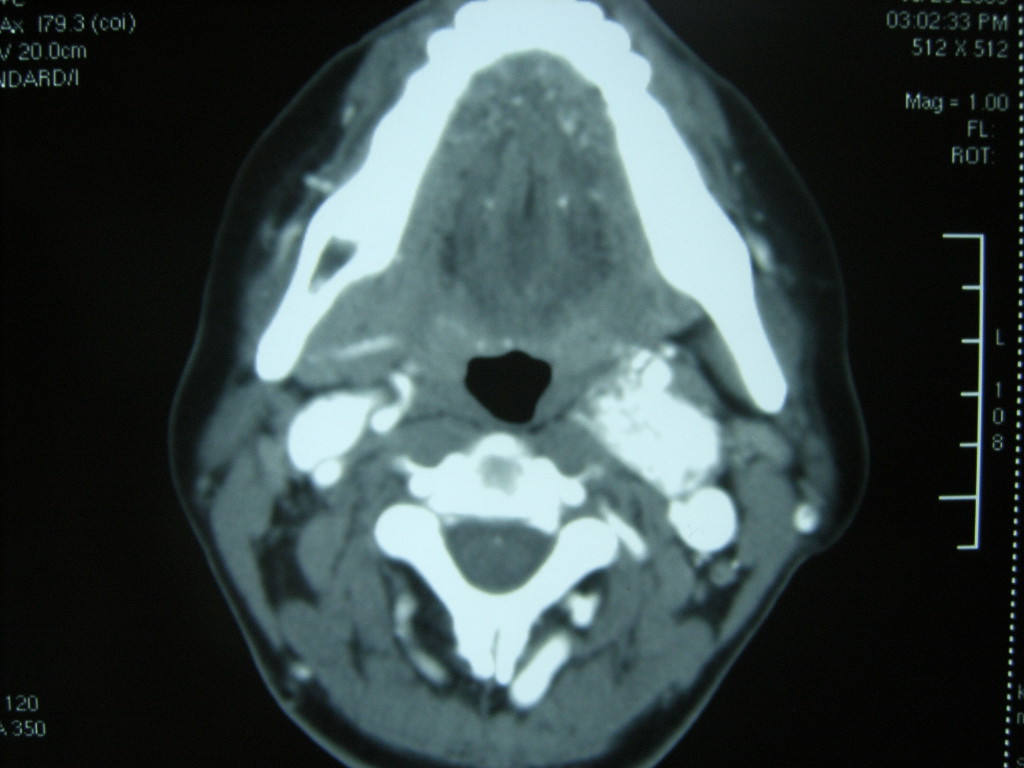

女,48岁,左颈部增粗,不适一年,伴左侧面麻.

增强明显,考虑左侧颈动脉体瘤可能性大。

答案:颈动脉体瘤  此患者已于赤峰220医院手术,